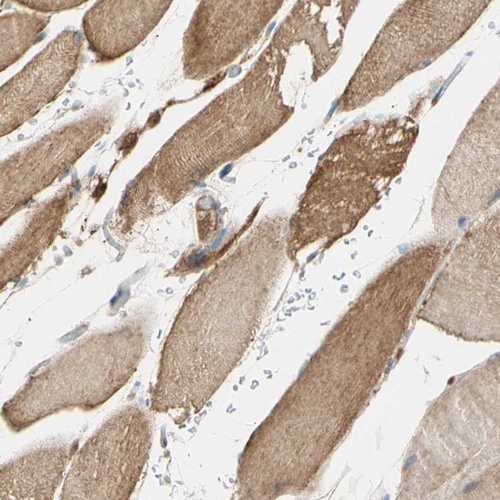

Immunohistochemical staining of human skeletal muscle shows cytoplasmic positivity in myocytes.